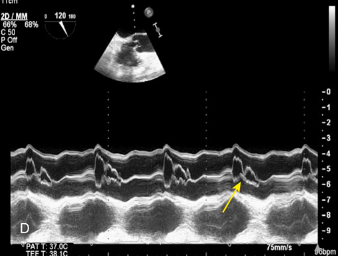

Oscillatory changes of the IVS

Constrictive pericarditis

What is the arrow pointing to?

What condition is this finding demonstrated in?